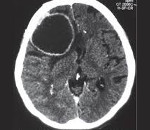

- Томографічні дослідження. Дозволяють виявити внутримозговое освіту з тонкими стінками, визначити його локалізацію і обсяг. КТ головного мозку більш інформативно щодо кальциноза капсули, МРТ головного мозку краще візуалізує стінки кісти.

Отримані результати оцінюють у сукупності, зіставляючи їх з клінічними симптомами і перебігом захворювання. Диференціювати ехінококоз головного мозку необхідно від інших об'ємних утворень: арахноідальних кіст , церебрального цистицеркоза , Епідермоїдний кіст, інтракраніальних пухлин і абсцесів.